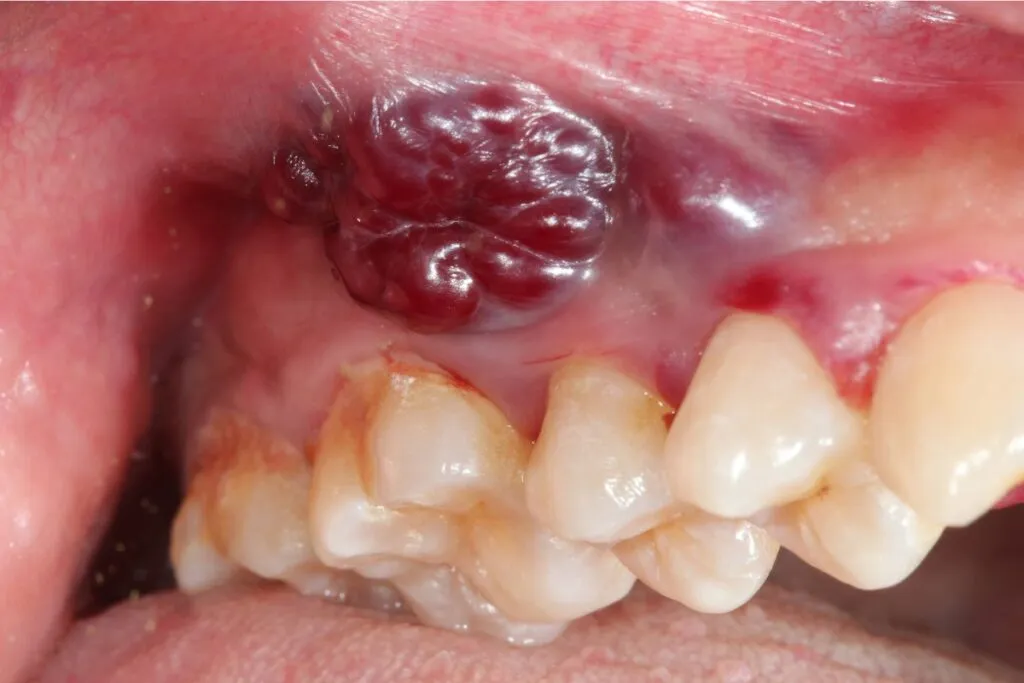

Rak płaskonabłonkowy to nowotwór złośliwy wywodzący się z komórek nabłonka płaskiego, które naturalnie wyściełają dużą część jamy ustnej. Jest to obszar szczególnie narażony na działanie wielu czynników drażniących, co sprzyja rozwojowi zmian nowotworowych. Najczęściej ten typ raka rozwija się na bocznej powierzchni języka, co stanowi około 40% przypadków, oraz w dnie jamy ustnej (około 30%). Inne typowe lokalizacje to błona śluzowa policzków, dziąsła, podniebienie twarde, a także warga. To właśnie w tych miejscach powinniśmy być szczególnie czujni na wszelkie niepokojące zmiany.

Z kolei erytroplakia to czerwone, aksamitne plamy, które również nie ustępują samoistnie. Są one znacznie bardziej alarmujące niż leukoplakia, ponieważ mają znacznie wyższy potencjał transformacji nowotworowej. Każda czerwona zmiana w jamie ustnej, która utrzymuje się dłużej niż kilka dni, powinna być natychmiast skonsultowana ze specjalistą.

Subtelne zgrubienie lub guzek: Jak wyczuć zmianę?

Rak płaskonabłonkowy może objawiać się również jako subtelne zgrubienie lub guzek w jamie ustnej, wyczuwalny dotykiem. Początkowo może być on zupełnie bezbolesny, co sprawia, że łatwo go przeoczyć podczas codziennej higieny. Nawet małe, niebolesne zmiany, które nie ustępują, powinny wzbudzić czujność i skłonić do samobadania, a następnie do konsultacji lekarskiej.